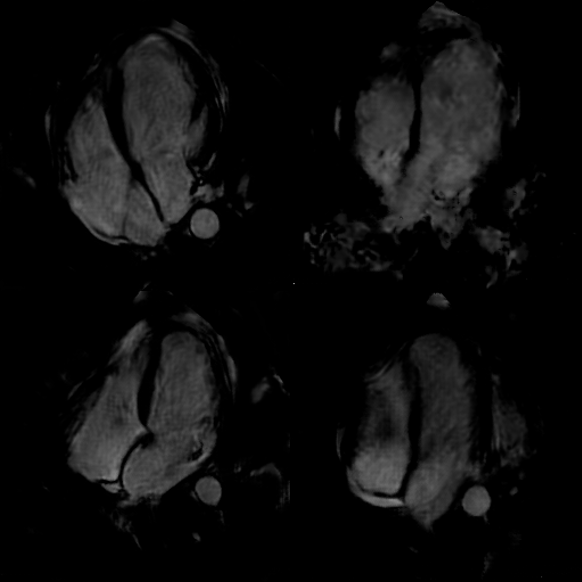

Refer to caption ABCD

Figure 34: Four samples from the confusion test, consisting of randomly selected synthetic and original cardiac MRI images. Cardiologists were asked to differentiate between the synthetic and original images. The samples include: A (original), B (original), C (synthetic), and D (synthetic).